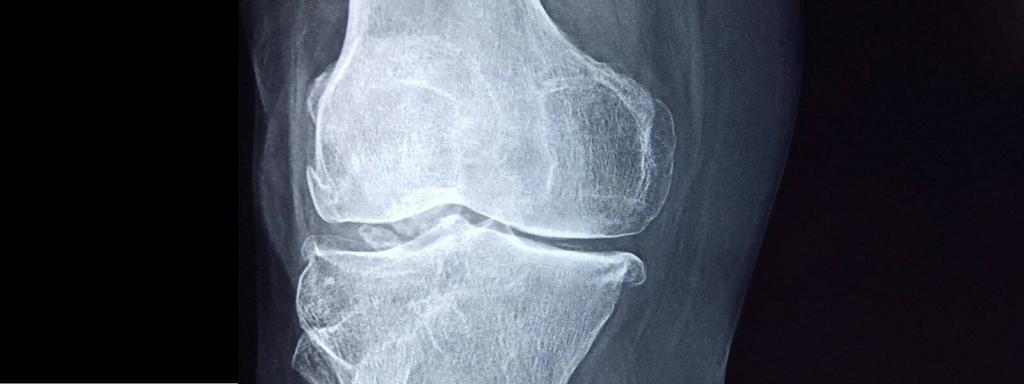

Can I make bone tissue separate from the human body? Kazakh scientists have launched a unique project to answer this question. A group of scientists from NU, led by Professor Dana Akylbekova, developed a new technology that allows you to grow human bones and print their 3D model. The existing process is carried out using a Swedish printer.